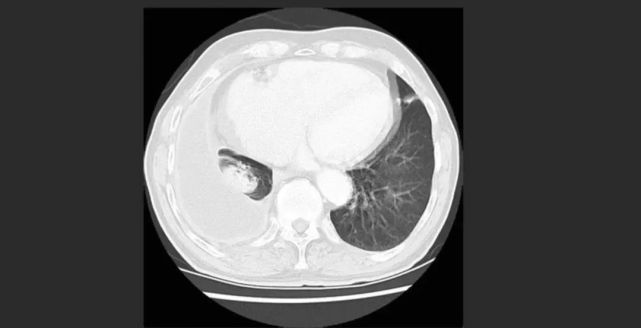

那为什么叫白肺呢?这是因为正常健康的肺,都是由通气功能正常的肺泡组成的,在X光和CT上都是透光的,并且显示为“黑色”。但如果肺部有严重的疾病(比如肺炎或者肺部肿瘤),或者有大量的胸腔积液,让健康的肺组织不再具有正常的通气和其他交换功能,肺泡组织被破坏了,这时候在X光和CT上就表现为“白色”。

一般情况下,我们说的白肺是指广泛的大面积的,至少累及到一个肺叶的病变,如果只是部分肺叶的改变,一般不称做白肺。